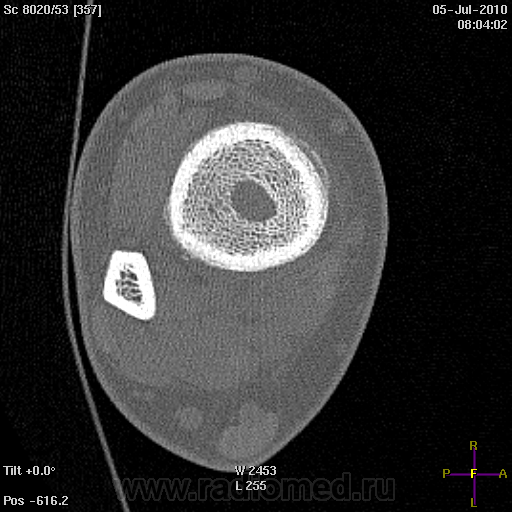

Вчера было проведено КТ-г/стопного сустава:

Только по рентгенограммам (без учета КТ) высказался-бы в пользу абсцесса Броди.

Да, "он" самый вчера сразу оперировали, опять в течении года нагрели, находился под наблюдением у ревматолога, неоднократное введение препаратов в сустав.

Так, абсцесс Броди?

После операции травматологи тоже поставили абсцесс Броди: "Выполнена трепанация, выделился густой сливкообразный гной без запаха. Трепанационное отверстие расширено до размеров 2,5*4 см. Полость вычищена, гной взят на посев, часть стенки абсцесса отправлена на гистологическое исследование. В получившуюся полость 4,5*2,5*3,5 см помещен цементный спейсер с антибиотиком"